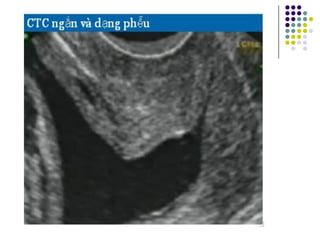

Đo chiều dài CTC: CTC dạng

phễu

- Khi lỗ trong mở trên siêu âm CTC sẽ có dạng

hình phễu ( biểu hiện của một quá trình CTC

ngắn lại)  kết quả sau cùng là sanh non

- Hầu hết các phụ nữ có CTC ngắn sẽ có lỗ

trong hình phễu

- Phụ nữ có CTC dài và hình phễu thì không

có nguy cơ sanh non